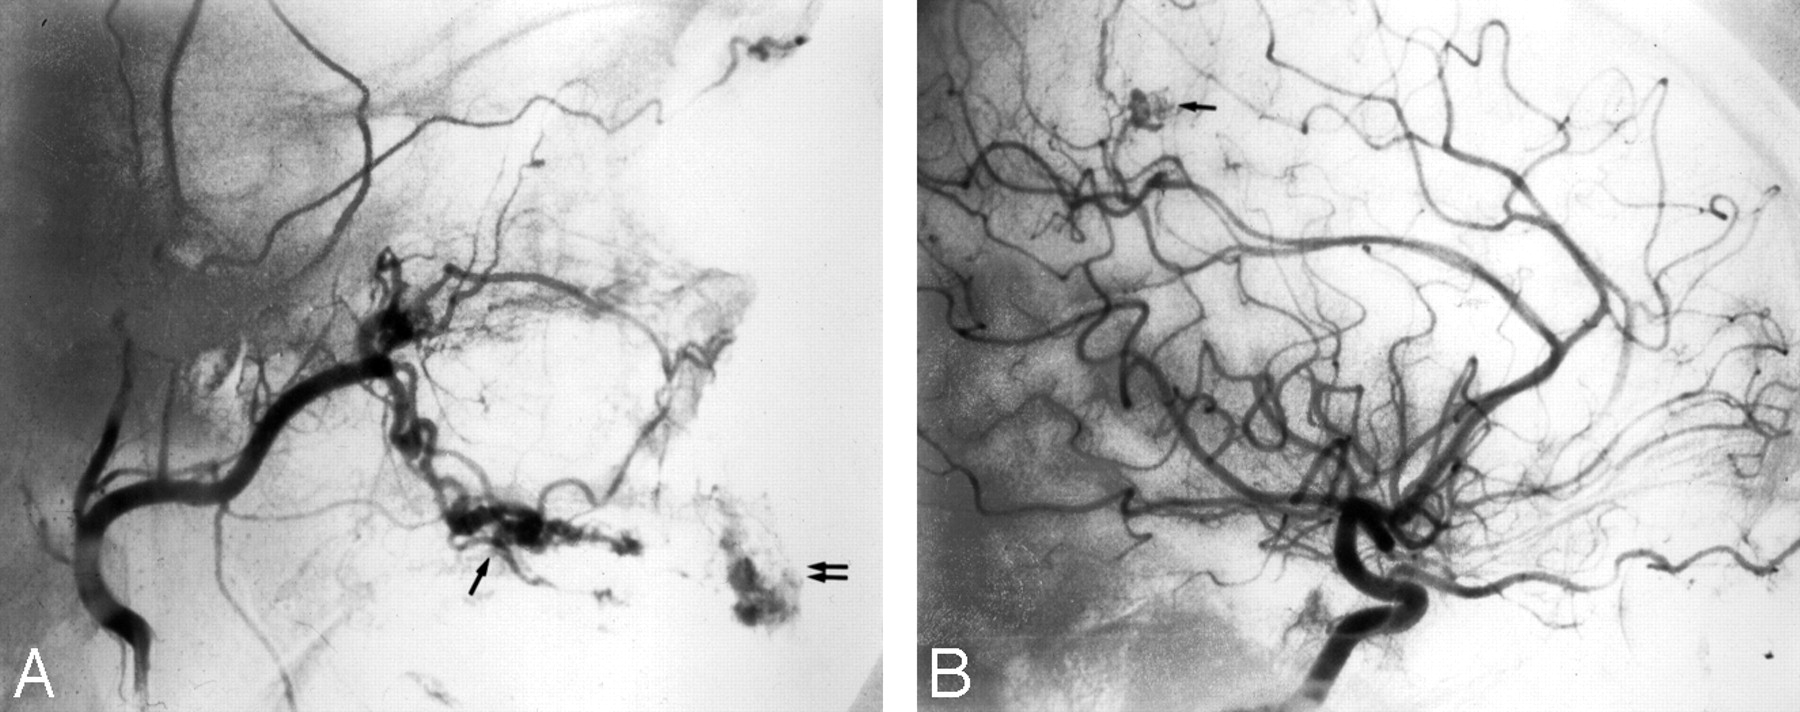

Хирургические процессы при эмболизации гемангиомы на фото

Раздел: Снимки-откровения